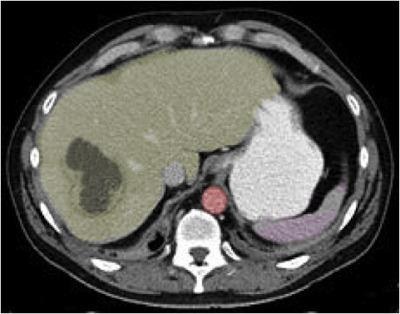

Gambar 2. Abses Hepar. Pada CT scan menunjukkan lesi hipodens [ada lobus dextra hepar